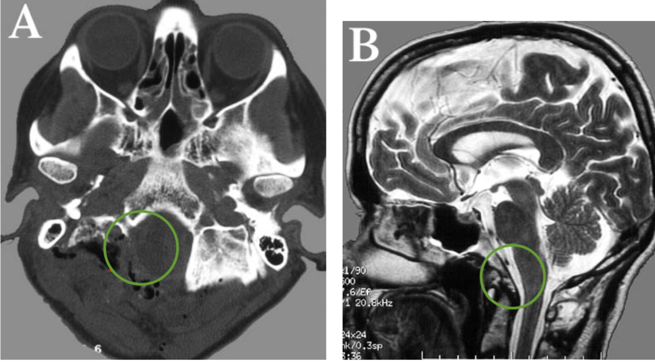

枕骨大孔区等位于颅底深部的脑膜瘤治疗难点在于难以切除干净...

枕骨大孔 脑膜瘤 怎么治疗?复发几率大吗?脑膜瘤是常见的...

斜坡脑膜瘤手术成功率是多少?风险大吗? 脑膜瘤 (Meningiomas)是...